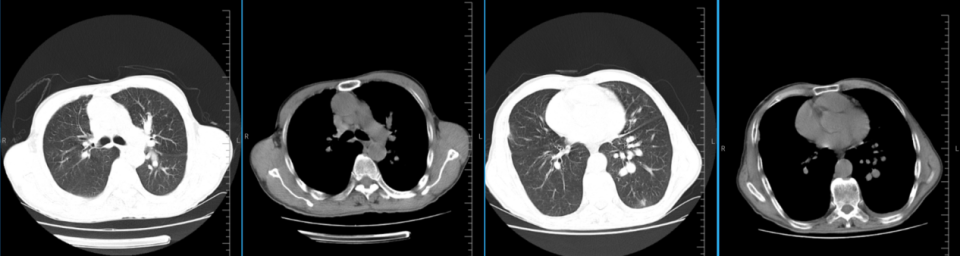

患者20余天前出现呼吸困难,活动后明显,有咳嗽、咳白痰。2025年7月30日,当地医院肺部CT提示“左肺感染伴左侧胸腔积液”,遂住院,行胸水引流,为淡黄色清亮液体。2025年8月1日胸水化验:总蛋白12.2g/L,LDH93U/L,单个核细胞93%,多个核细胞 7%,李凡他试验阴性,且胸水病理未找到肿瘤细胞。外院予左氧氟沙星抗感染治疗,治疗后复查胸部CT左肺感染及胸腔积液基本吸收(胸水引流前后CT见图1a、图1b),后出院。

图1a:2025.07.30外院胸腔积液穿刺前CT

图1b:2025.08.06外院胸腔积液穿刺后CT

图22025.08.13我院急诊CT:左肺散在炎症,左侧胸腔大量积液伴左肺大部不张实变